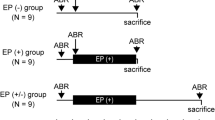

3.3 Reintroduction of Neural Activity via Cochlear Implants

Neural activity has been found to be extremely important for normal postnatal development and maintenance of sensory systems (Wiesel & Hubel, 1963; Van der Loos & Woolsey, 1973). Indeed, the process of hearing is necessary for refinement of the genetic blueprint for auditory circuitry, including axonal distribution, pruning, and synapse formation (Parks et al., 2004; Shepherd et al., 2006; Walmsley et al., 2006; Ryugo & Limb, 2009; Sanes & Bao, 2009). Deprivation of auditory experience can introduce a series of pathologic and atrophic changes that include more widespread distributions of axonal projections (Leake et al., 2006), abnormal projections (Nordeen et al., 1983a,b; Moore & Kitzes, 1985), delayed maturation (Sanes, 1993; Kandler, 2004), and language impairments (Robbins, 2006).

When experiential deprivation can be traced to the malfunction of a sensory end organ, it may be possible to reintroduce sensation via direct stimulation of the remaining neural circuits, bypassing the impaired receptors. The cochlear implant works on this principle by directly stimulating SG cells, thus restoring activity to the auditory pathway (Rauschecker & Shannon, 2002). Not long after serious development began on electrical auditory prostheses for human use, the potential of the congenitally deaf cat was recognized as a model for examining the central effects of cochlear implantation (Elverland et al., 1975). Various methods have been used to reintroduce sound-evoked activity to genetically and neonatally deafened cats (Matsushima et al., 1991; Lustig et al., 1994; Klinke et al., 1999), including a miniaturized six-channel cochlear implant that utilizes a speech processor identical to that used with human patients (Kretzmer et al., 2004). With such devices, cats have been trained with food rewards to respond to specific sounds, indicating that behaviorally relevant signals are being processed (Klinke et al., 1999; Kretzmer et al., 2004; Ryugo et al., 2005; O’Neil et al., 2010). For instance, animals were trained to approach their food bowls in response to a specific bugle call, but not other bugle calls. Importantly, the bugle call required specific spectral content, as monotonic calls with the same rhythmic structure failed to elicit a behavioral response.

Endbulbs were studied in congenitally deaf cats that were given implants at 3 and 6 months of age (Fig. 1; Ryugo et al., 2005; O’Neil et al., 2010). In young-implanted animals, synapse restoration was evident in endbulbs ipsilateral to stimulation (Fig. 7, bottom; Ryugo et al., 2005; O’Neil et al., 2010). PSDs returned to their smaller size and were statistically identical to those of normal hearing cats. The PSDs also regained their normal dome-shaped curvature. The endbulb itself appears to regain some degree of its complexity; normal numbers of boutons are observed, but they remain larger than those of normal cats (Fig. 8; O’Neil et al., 2011). Modest improvements were also observed at synapses of the contralateral auditory nerve, though the exact mechanism for this benefit remains unknown (O’Neil et al., 2010). Synaptic recovery, however, was not observed in the late-implanted, 6-month-old group (O’Neil et al., 2010). This result suggests that the rescue of synapses may be possible only during the “critical” developmental period preceding puberty, occurring around 6 months of age (Fig. 8), an observation with clear clinical implications for implantation in children. The restoration of endbulb synapses is hypothesized to represent the first link for the proper delivery of afferent signals to the central auditory system in a timely, coherent, and synchronized way.

Auditory cortex of the congenitally deaf cat retains aspects of ascending input circuitry. Electrical stimulation of the auditory nerve produces clear cortical activations, and has been used to reveal a rudimentary cochleotopic organization (Hartmann et al., 1997) as well as a latent, albeit diminished, sensitivity to ITDs (Tillein et al., 2010). Deafness also affects cortical spatiotemporal response dynamics and contralateral dominance (Kral et al., 2009). Current source density analysis of evoked local field potentials shows significant deficiencies in the layer-specific activation patterns of deaf adults, especially in deeper layers (Kral et al., 2000), and this activation pattern develops in an abnormal fashion over the first few postnatal months (Kral et al., 2005). Cochlear implantation of young (Klinke et al., 1999), but not older (Kral et al., 2001), cats results in cortical recruitment indicative of more normal processing, including sound-evoked behaviors, and the amount of recruitment correlates with age (Kral et al., 2002).

5 Functional Outcomes

The concept of the critical period describes biological phenomena that occur or are most severely affected within a limited time window of development. This has been elegantly demonstrated by the imprinting experiments of Lorenz (1935) and applied to observations such as cortical barrel plasticity (Van der Loos & Woolsey, 1973; Weller & Johnson, 1975), the surgical repair of monocular amblyopia (Raviola & Wiesel, 1985), birdsong acquisition (Konishi, 1985), and the functional maturation of auditory cortex (Chang & Merzenich, 2003; de Villers-Sidani et al., 2007). Clinical reports indicate that young children receiving cochlear implants gain superior benefits when compared to older children and adults, drawing support for the idea of a critical period for the proper maturation of hearing (Gantz et al., 1994; Waltzman et al., 1994; Tyler & Summerfield, 1996; reviewed by Francis & Niparko, 2003). Decades of research from animal models of deafness clearly demonstrate a need for auditory experience from an early age for the initial formation of precise synaptic structure, functional organization, and proper distribution of terminals all along the ascending auditory pathways.

Timing cues are critical for recognizing speech in conditions where spectral content is severely degraded (Shannon et al., 1995). In congenitally deaf cats, temporal information is corrupted at the first synapse by malformations of the endbulb (Ryugo et al., 1997, 1998) and presumably exacerbated further by the inappropriate balance of excitation and inhibition in the MSO (Tirko & Ryugo, 2012). Electrical stimulation has revealed some of the consequences of these, and likely other, synaptic deficits: impaired processing of ITD cues in the inferior colliculus (Hancock et al., 2010) and reduced and smeared responses in the auditory cortex (Kral et al., 2000). Implant-induced synaptic plasticity can restore some of these morphological and physiological impairments, but, at least in deaf white cats, only if performed within the developmental period preceding puberty (Kral et al., 2001; O’Neil et al., 2010), echoing clinical observations with children (Francis & Niparko, 2003; Kral & Sharma, 2012).

Implantation, however, does not yet restore all functionality in hearing. In implanted cats, electrically evoked ABR waveforms are somewhat delayed and flattened relative to normal hearing cats (Kretzmer et al., 2004). This pathologic waveform suggests diminished synchrony in the evoked responses, perhaps caused by an increase in transmission jitter failure. It is possible, however, that stimulation for a longer period would have resulted in more normal responses. Clinical evidence shows that patients with bilateral implants regain some benefits of binaural hearing, such as sound localization and improved speech perception in noisy environments, but are still largely unable to use ITD cues, instead relying disproportionately on ILD signals (van Hoesel, 2004; Seeber & Fastl, 2008). Further, this inability is graded with the age at onset of deafness: Patients who lost their hearing later in life showed some sensitivity to ITDs, whereas those who became deaf early were largely insensitive to ITDs (Litovsky et al., 2010). Measures of ABR responses in young children also show prolonged latencies in the responses between the two ears when the second implant is received more than two years after the first (Gordon et al., 2008). These results support the idea that the proper maturation of binaural pathways is dependent on auditory experience from both ears.